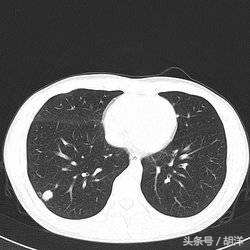

肺结核是一种常见的传染病,是由于结核菌感染造成的肺部结构破坏性疾病,其发生不单单有结核菌在肺部生长增殖并破坏肺部结构的因素,也有免疫细胞在与结核菌相互作用释放一些酶类造成肺部损害的因素,肺结核常常会出现钙化灶,特别是以往患有结核愈合后留下的疤痕,常常以钙化的形式存在,可以这么说钙化灶是肺结核愈合的表现,或者是陈旧性病灶的标志。

大部分情况下,病灶中只要有活的结核菌就不会出现钙化病灶,因为能够产生钙质的细胞不能在活动性结核病灶中存活,所以只要出现钙化,说明分泌钙质的细胞在病灶中站稳了脚跟并开始分泌钙质正常工作,病灶中要么结核菌已经被清除,要么出于休眠期。

肺部的病灶如果其中有钙质,特别是钙质出于病灶的中间部位或者占病灶体积的绝大多数,则恶性的可能性比较小,如果钙化部位出于病灶的边缘或者偏于一侧,则并不能完全排除肿瘤的可能性。

钙化灶是肺部损伤病灶的修复机制,出现钙化大部分说明病灶中的病原体已经没有活性,在鉴别诊断中,钙化灶大多数时候是排除肿瘤的特征性标志。